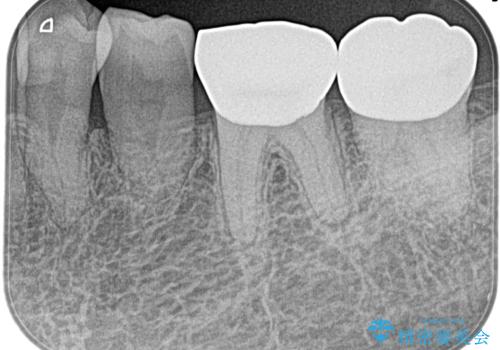

奥歯がズキズキ痛い 根管治療

担当医 河口智英